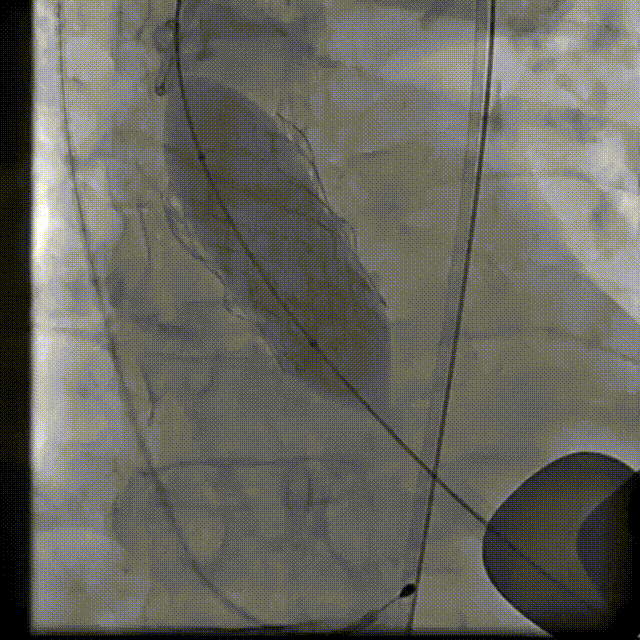

主动脉根部造影

18 mm球囊预扩张

输送系统到位

瓣膜交界对齐释放

22 mm球囊后扩

最终造影